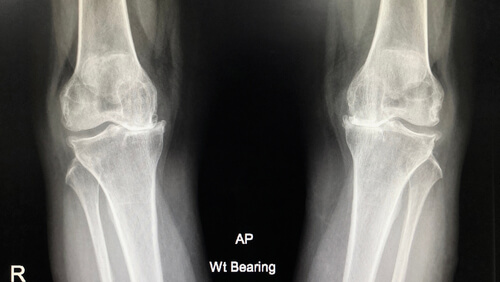

X-ray is the reference to confirm the diagnosis of knee osteoarthritis and grade its severity. Ultrasound and MRI may also be used.

osteoarthritis x ray